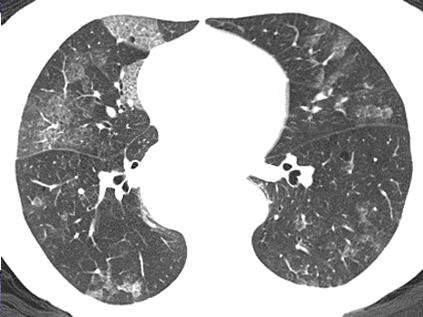

間質(zhì)性肺病(Interstitial lung Disease,簡稱ILD) 是以彌漫性肺實(shí)質(zhì)、肺泡炎和間質(zhì)纖維化為病理基本改變,以活動性呼吸困難、X 線胸片示彌漫陰影、限制性通氣障礙、彌散功能(DLCO)降低和低氧血癥為臨床表現(xiàn)的不同類疾病群構(gòu)成的臨床病理實(shí)體的總稱。ILD 通常不是惡性的,也不是由已知的感染性致病源所引起的。繼發(fā)感染時可有黏液濃痰,伴明顯消瘦、乏力、厭食、四肢關(guān)節(jié)痛等全身癥狀,急性期可伴有發(fā)熱。